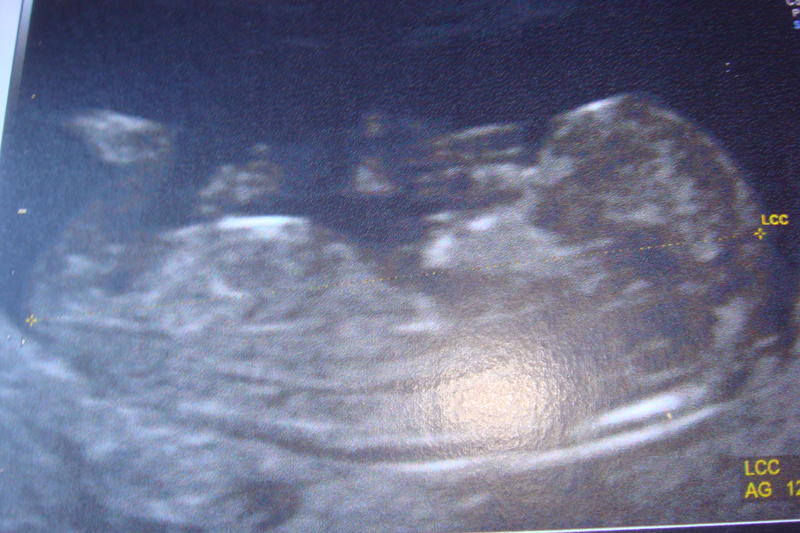

et une de mon 4eme petit bout echo faite la semaine derniere a 12sa!! 90 pourcent de chance que sa sois un petit mec!! puff j ai deja 3 petits mec alors un de plus...mdr!!